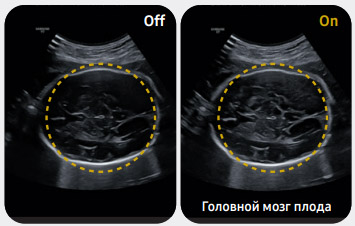

Автоматическая классификация и маркирование изображений

Функция ViewAssist™, основанная на технологии глубокого обучения, автоматически классифицирует ультразвуковые изображения и маркирует анатомические структуры плода.

Автоматизированная фетометрия

Функция фетометрии BiometryAssist™ основана на технологии глубокого обучения. Она позволяет одним нажатием кнопки измерить параметры роста плода, не прерывая исследование.